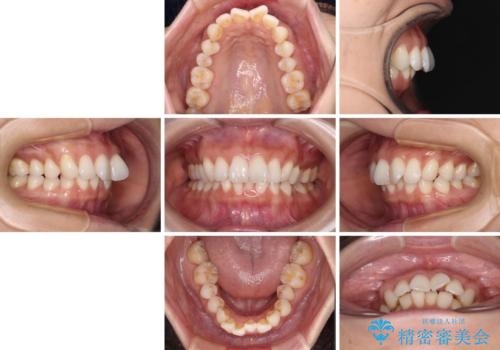

- 前歯の突出感とデコボコを気にして来院された患者様です。

奥歯の噛み合わせをみると、上顎歯列が全体的に前突している状態であり、この咬み合わせのまま歯列を整えると出っ歯になってしまう可能性がありました。

アンカースクリューと補助装置を使用して上顎大臼歯を遠心移動させることで咬み合わせを改善し、ワイヤー装置によりデコボコを解消しながら口元の突出感も改善していくこととしました。